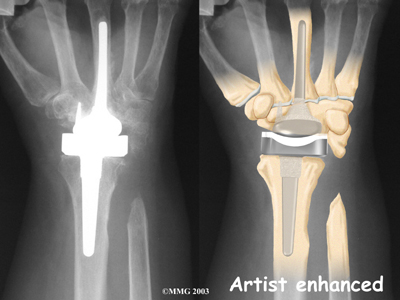

Modern artificial wrist joints are made of metal and plastic. The part that fits against the end of the radius bone of the forearm is called the radial component. It is made up of two pieces. A flat metal piece is placed on the front part of the radius. It has a stem that attaches down into the canal of the bone. A plastic cup fits onto the metal piece, forming a socket for the artificial wrist joint.

The part that replaces the small wrist bones is called the distal component. This piece is made completely of metal. It is globe shaped to fit into the plastic socket on the end of the radius. The metal distal component is attached by two metal stems that fit into the hollow bone marrow cavities of the carpal and metacarpal bones of the hand.

The plastic used in artificial joints is tough and slick. It allows the two pieces of the new joint to glide easily against each other as you move your wrist. The ball and socket allow movement of the wrist in all directions.

Replacement Joint

The surgeon will take some time to get the stems to fit tightly. The joint is put in place and tested through its range of motion to make sure it moves correctly. Once the surgeon is satisfied with the fit, the stems of each metal implant are:

Cemented into Place